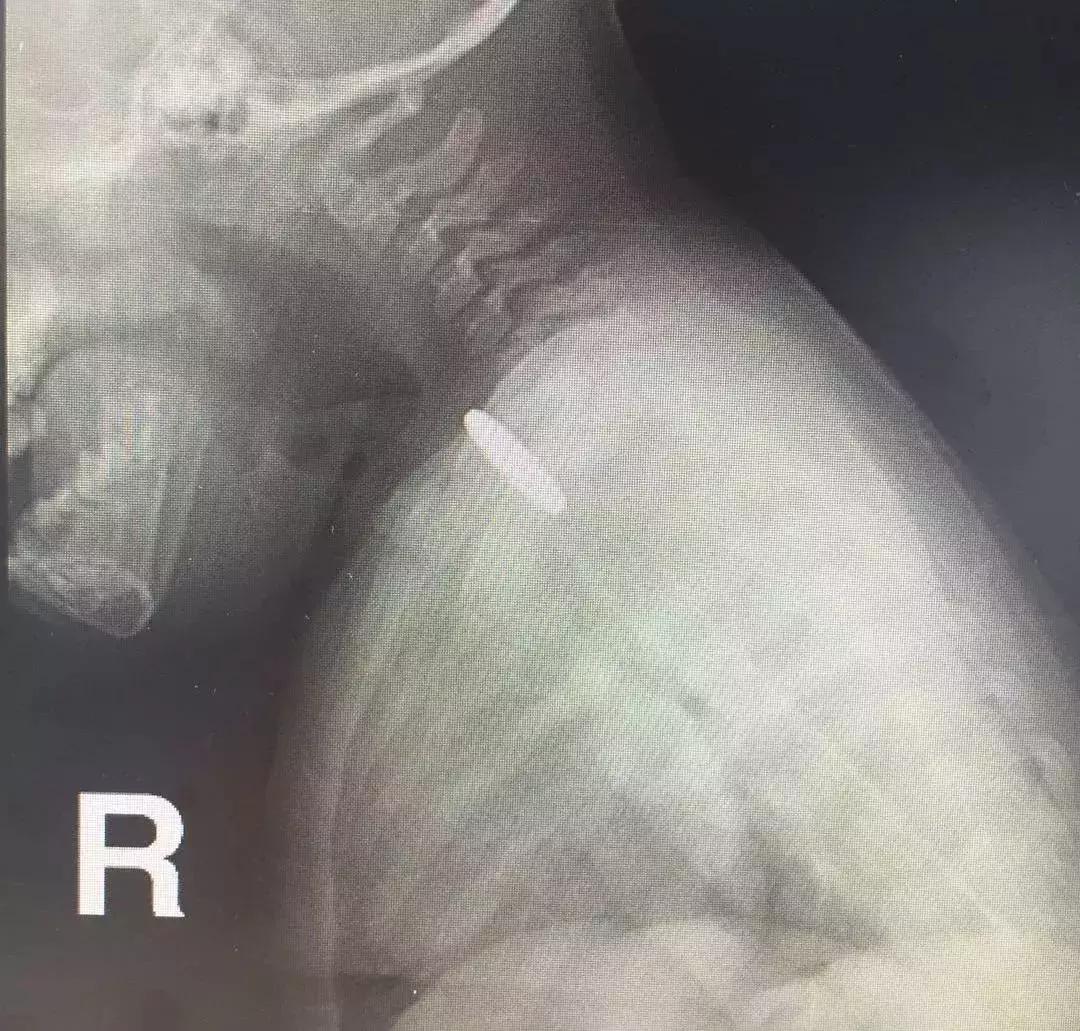

麻醉科文先杰博士决定为心心做气管插管麻醉,堵住可能存在的风险点。气管插管是指将一特制的气管内导管经口腔或者鼻子置入气管,以保证气道通畅。

由于孩子的气道很很窄,小儿气管插管并非一件易事。但是,文先杰博士凭借过硬的技术顺利完成。

孩子的食管很窄,尤其是食道入口位置不足1厘米,消化内科副主任医师陈渭选用了最小的8毫米直径的内镜。

慢慢进入,在食道入口处见到了那枚堵住食管的硬币,观察到心心的食道没有损伤之后,用专用的异物钳小心翼翼取出硬币,一气呵成,全程不到2分钟,整个过程患儿并没有痛苦。